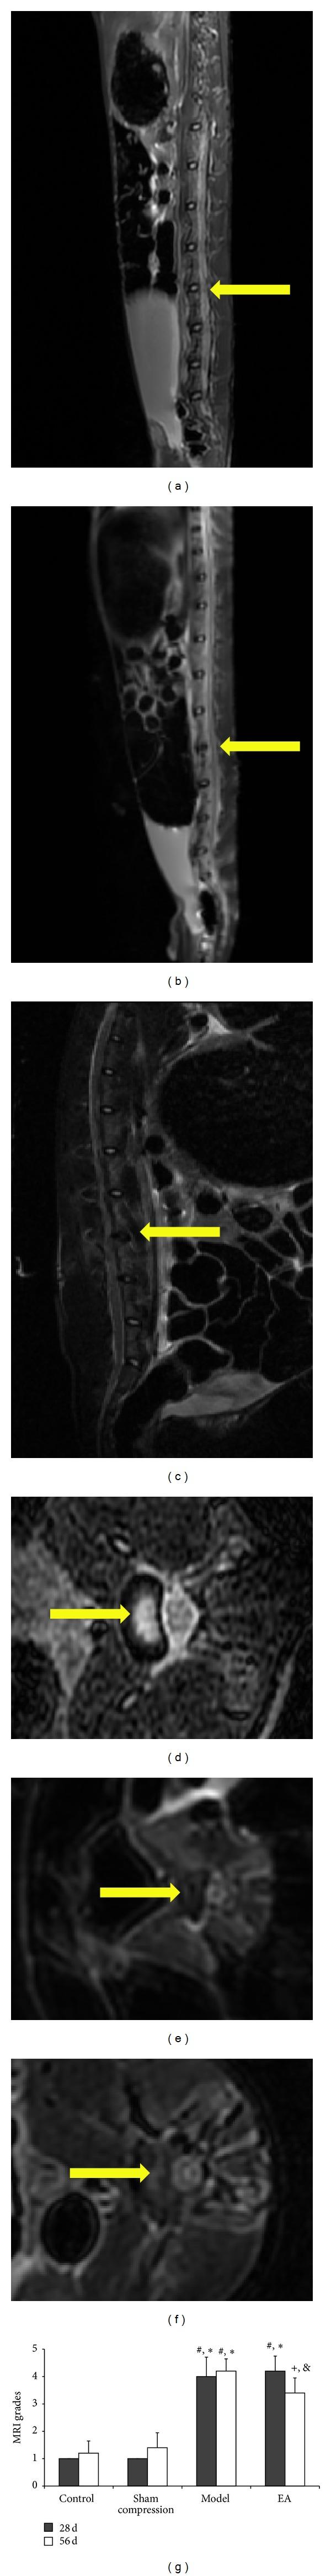

The present study was aimed at determining if the electroacupuncture (EA) is able to protect degenerated disc in vivo. New Zealand white rabbits (n = 40) were used for the study. The rabbits were randomly assigned to four groups. EA intervention was applied to one of the four groups. Magnetic resonance imaging and Pfirrmann's classification were obtained for each group to evaluate EA treatment on the intervertebral disc degeneration. Discs were analyzed using immunofluorescence for the labeling of collagens 1 and 2, bone morphogenetic protein-2 (BMP-2), matrix metalloproteinase-13 (MMP-13), and tissue inhibitor of matrix metalloproteinase-1 (TIMP-1). For protein expression analysis, western blot was used for biglycan and decorin. Outcomes indicated that EA intervention decreased the grades compared with the compressed disc. Immunofluorescence analysis showed a significant increase of collagens 1 and 2, TIMP-1, and BMP-2 positive cells, in contrast to MMP-13 after EA treatment for 28 days. The protein expression showed a sign of regeneration that decorin and biglycan were upregulated. It was concluded that EA contributed to the extracellular matrix (ECM) anabolic processes and increased the ECM components. MMPs and their inhibitors involved in the mechanism of EA intervention on ECM decreased disc. It kept a dynamic balance between ECM synthesis and degradation.

本研究旨在确定电针对体内退变椎间盘是否具有保护作用。选用新西兰大白兔(n = 40)进行研究。将兔子随机分为四组。对其中一组进行电针干预。对每组进行磁共振成像和 Pfirrmann 分级,以评估电针对椎间盘退变的治疗作用。采用免疫荧光法对椎间盘进行胶原 1 和 2、骨形态发生蛋白 2(BMP-2)、基质金属蛋白酶 13(MMP-13)和基质金属蛋白酶抑制剂 1(TIMP-1)的标记分析。采用 Western blot 法分析 biglycan 和 decorin 的蛋白表达。结果表明,与受压椎间盘相比,电针干预降低了分级。免疫荧光分析显示,电针治疗 28 天后,胶原 1 和 2、TIMP-1 和 BMP-2 阳性细胞显著增加,而 MMP-13 则减少。蛋白表达显示出再生的迹象,decorin 和 biglycan 上调。结论:电针促进细胞外基质(ECM)合成代谢过程,并增加 ECM 成分。参与电针对 ECM 干预机制的 MMPs 及其抑制剂可减少椎间盘退变。它在 ECM 的合成和降解之间保持了动态平衡。